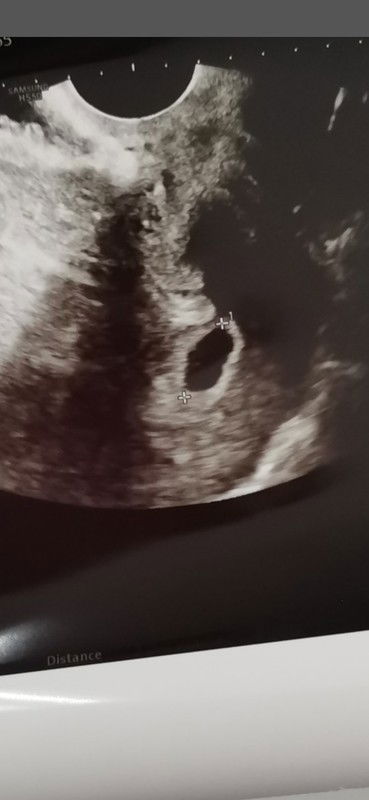

้บ้านนี้ไปฝากครรภ์ครั้งแรกเมื่อเช้าคุณหมอบอกว่าคุณแม่ท้องได้7วีคน่ะค่ะ หมอเลยซาว์ด เจอ หัวใจเต้น ถุงการตั้งครรภ์ เล็กมากๆๆมองไม่ค่อยชัดค่ะ

เจอน้องตอน 5 w น้องยังเท่าเม็ดถั่วเล็กๆ เองค่ะ เจอหัวใจตอน 6 w บางคนเจอช้าเจอเร็วไม่เหมือนกันนะคะ ขอให้คุณแม่และน้องแข็งแรงๆน๊า 🥰

อันนี้รูปตอน 5w ค่ะ แต่ตอนนี้อายุครรภ์ 25w แล้วค่ะ ยินดีกับคุณแม่ทุกท่านด้วยนะคะ ขอให้แข็งแรงทั้งคุณแม่และเจ้าตัวน้อยน๊าาา

บ้านนี้เจอตอน8วีคค่ะ ไปครั้งแรกตอน6วีคเจอแค่ถุงการตั้งครรภ์ พอ8วีคเจอน้องเจอหัวใจน้องแล้วค่ะ รอน้องก่อนนะ น้องกำลังโต 🥰

บ้านนี้ไปรอบแรกตอน6วีคเจอแต่ถุงน้ำค่ะ หมอนัดมาอีกทีตอน8วีคก็เจอตัวน้องแล้วก็เสียงหัวใจค่ะ